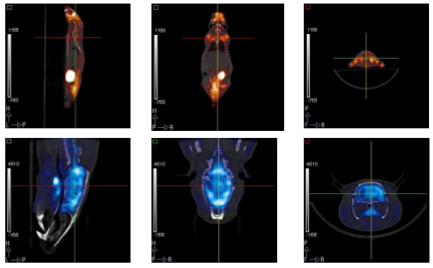

This work reports on the development and evaluation of the PET component of a PET/CT system for small-animal in-vivo imaging. The PET and CT subsystems are assembled in a rotary gantry in such a way that the center of rotation for both imaging modalities is mechanically aligned. The PET scanner configuration is based on 2 detector modules, each of which consist of 2 flat-panel type PS-PMTs (Hamamatsu, H8500) and 2 (30 × 30 elements) LYSO arrays.

|

Este trabajo describe el proceso de desarrollo y la evaluación inicial de un nuevo sistema tomográfico PET/CT de alta resolución, enfocado a la realización de estudios preclínicos “in-vivo” con animales de laboratorio. En el diseño implementado, los centros geométricos de cada modalidad de imagen están alineados mecánicamente permitiendo la obtención de conjuntos de datos con información anatómica y funcional que se registran y fusionan de forma automática.